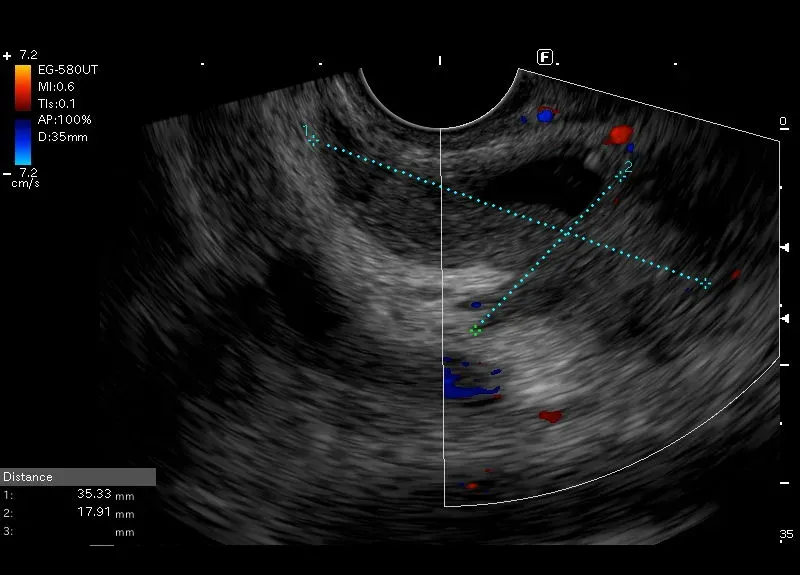

Widoczny w okolicy głowy trzustki przewód żółciowy wspólny o pogrubiałej (4 mm ścianie) łączącej się bez wyraźnej granicy z nieregularnym naciekiem około 36/18 mm, o zatartych granicach i obniżonej echogeniczności, przechodzącym na głowę trzustki. Obraz może odpowiadać nowotworowi dróg żółciowych z naciekaniem trzustki.